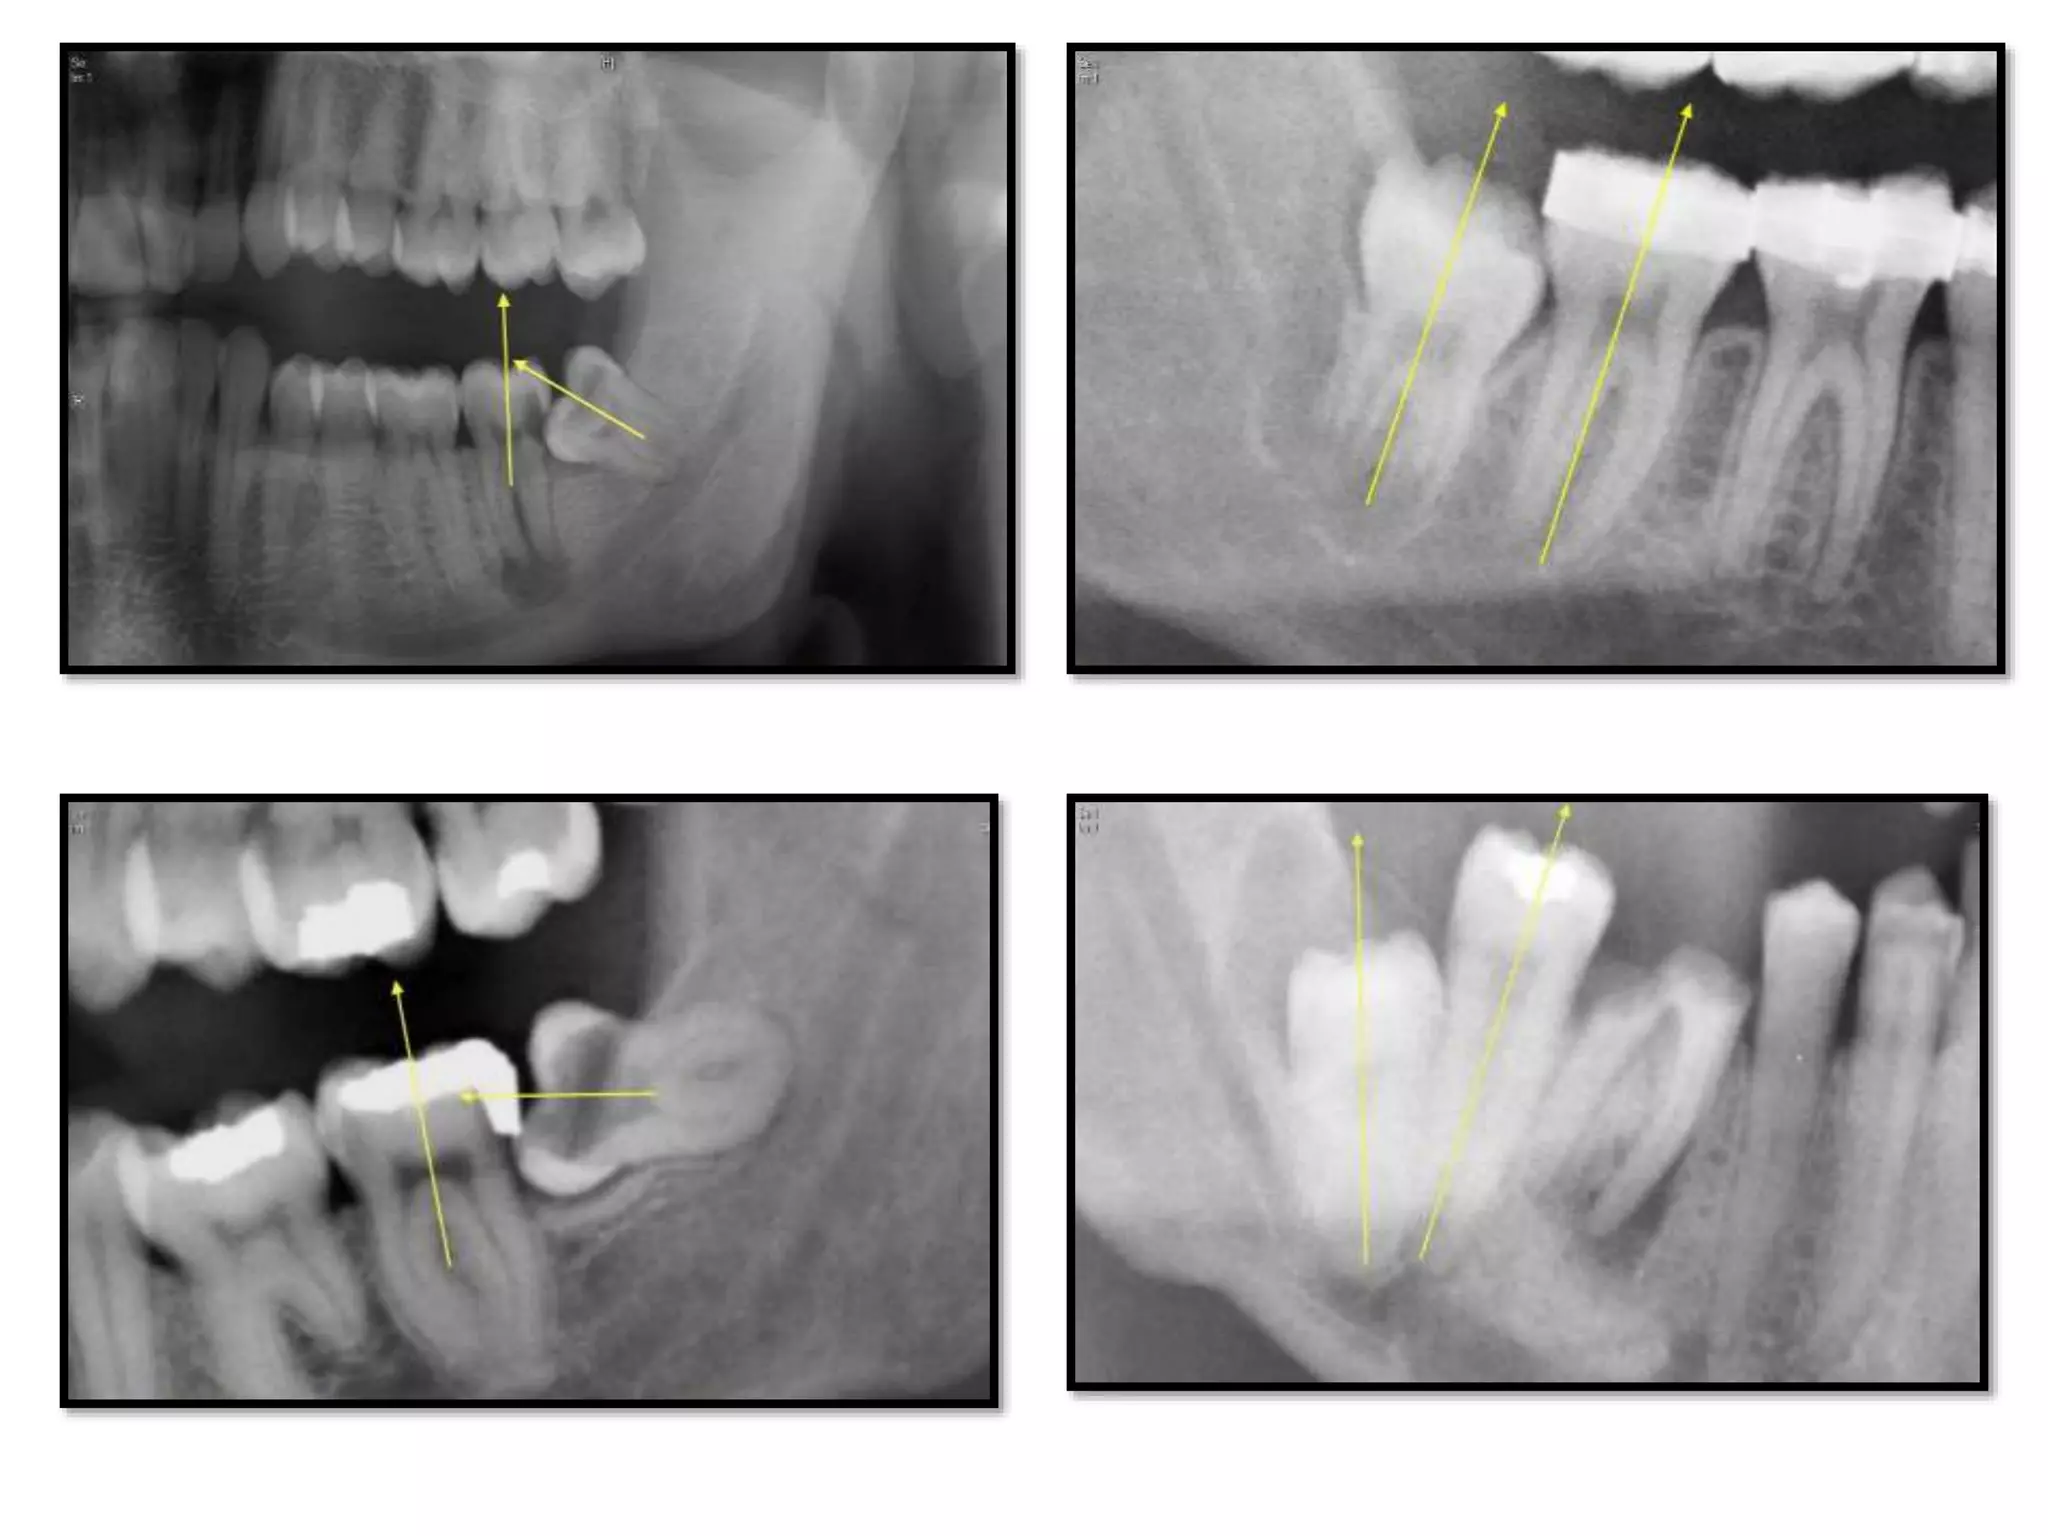

Operative Classification of Impacted

Molars (2010)

• The mandibular third molar is classified

according to its position relative to the

mandibular canal using a standard

panoramic x-ray.

• There are 3 major types of third molar

positions.

TMC I Roots of the third molar above the

mandibular canal

TMC IIa Mandibular third molar roots are in

relation to the mandibular canal

TMC IIb More than a third of the molar roots

are in relation to the mandibular

canal

TMC III All third molars roots are localized

below the mandibular canal

TMC I TMC II a

TMC IIITMC IIb